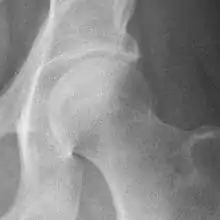

The most commonly used radiographic classification system for osteoarthritis of the hip joint is the Kellgren–Lawrence system (or KL system).[6] It uses plain radiographs.

Grade | Description |

---|---|

0 | No radiographic features of osteoarthritis |

1 | Possible joint space narrowing (normal joint space is at least 2 mm at the superior acetabulum)[7] and osteophyte formation |

2 | Definite osteophyte formation with possible joint space narrowing |

3 | Multiple osteophytes, definite joint space narrowing, sclerosis and possible bony deformity |

4 | Large osteophytes, marked joint space narrowing, severe sclerosis and definite bony deformity |

Osteoarthritis of the hip joint may also be graded by Tönnis classification. There is no consensus whether it is more or less reliable than the Kellgren-Lawrence system.[8]